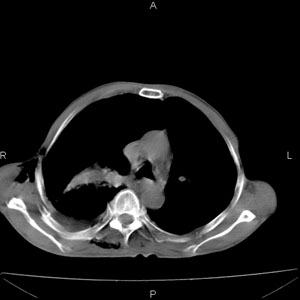

患者男,77岁,于3日前从树上摔下,头部查ct示蛛血,硬膜下出血,上腹部ct未见明显异常,右侧胸腔积液,左侧如常。肺部拍片示右侧肋骨多发骨折住院后今日来查肺部ct,我看到的是1。右侧胸腔血气胸并右肺上叶,中叶压缩性肺不张,2。右肺下叶肺挫伤并多发肋骨骨折,肌内及皮下积气3。左侧少量胸腔积液,我想请教的是3天前左侧胸腔里没有积液今天怎么出现了呢,是什么原因呢?请讨论。